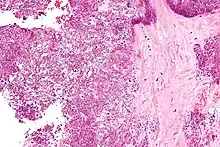

Polarized light microscopy of CPPD, showing rhombus-shaped calcium pyrophosphate crystals with positive birefringence.

Arthrocentesis, or removing synovial fluid from the affected joint, is performed to test the synovial fluid for the calcium pyrophosphate crystals that are present in CPPD. When stained with H&E stain, calcium pyrophosphate crystals appears deeply blue ("basophilic").[16][17] However, CPP crystals are much better known for their rhomboid shape and weak positive birefringence on polarized light microscopy, and this method remains the most reliable method of identifying the crystals under the microscope.[18] However, even this method has poor sensitivity, specificity, and inter-operator agreement.[18]